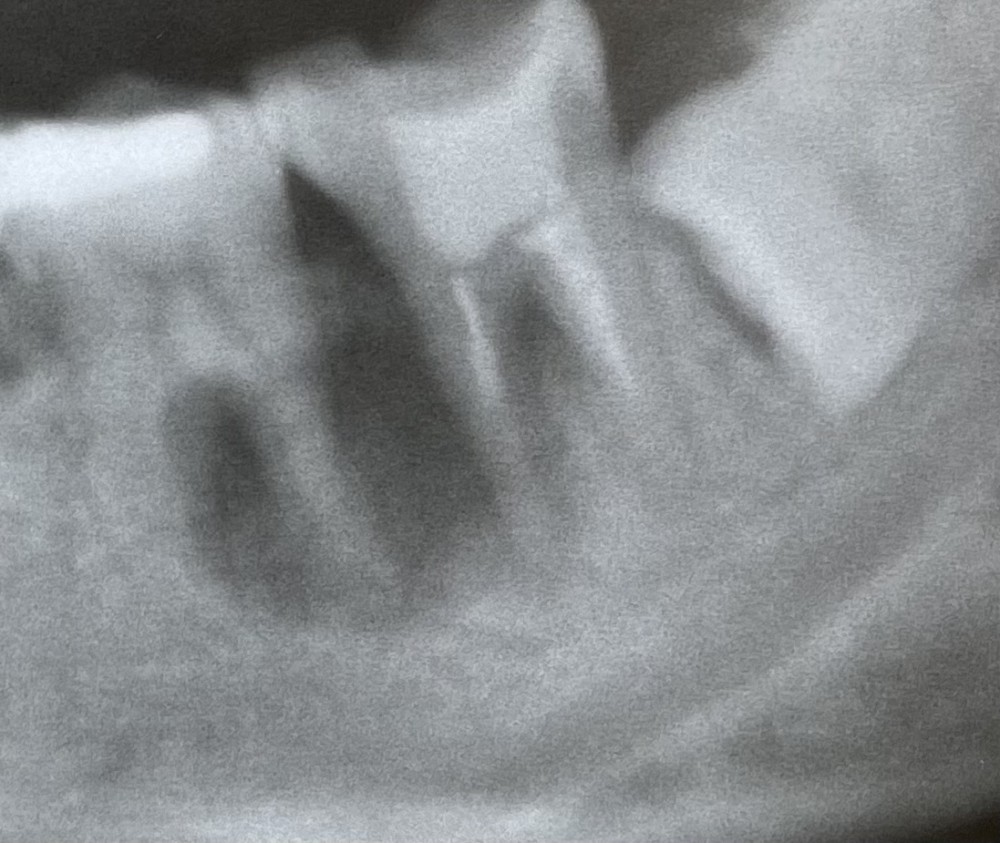

こちらのエックス線写真は、ある20代後半の患者さまのものです。

令和4年4月初診。左下奥歯の歯茎の腫れと痛みを伴い、当院に来院されました。

左下奥歯の下顎骨の部分のエックス線写真です。

楕円形に見える黒い部分に病巣が写っています。

病巣は2本の奥歯にまたがっているため、

病巣の原因となった歯を特定するのが困難な状況です。